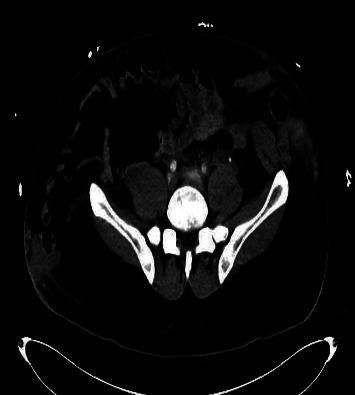

Garrett and Braunstein introduced the concept of the "seat belt sign" in motor vehicle collision (MVC) victims. They defined this as abdominal wall bruising from a lap belt. These signs of trauma are not uncommon. However, "seat belt syndrome," a pattern of musculoskeletal and internal organ injuries resulting from deceleration forces exerted by the safety device is rarely seen. Here, we illustrate a case of traumatic closed rupture of the rectus abdominis muscle secondary to seat belt injury. This potential injury is important to recognize and our case will illustrate the need for careful imaging review and clinical assessment to identify associated intra-abdominal injuries.

加勒特和布劳恩施泰因提出了机动车碰撞(MVC)受害者“安全带征”的概念。他们将其定义为安全带导致的腹壁瘀伤。这些创伤迹象并不罕见。然而,“安全带综合征”,即由安全装置施加的减速力导致的肌肉骨骼和内部器官损伤模式却很少见。在此,我们举例说明一例因安全带损伤继发腹直肌创伤性闭合性破裂的病例。认识到这种潜在损伤很重要,我们的病例将说明需要仔细进行影像学检查和临床评估,以识别相关的腹腔内损伤。